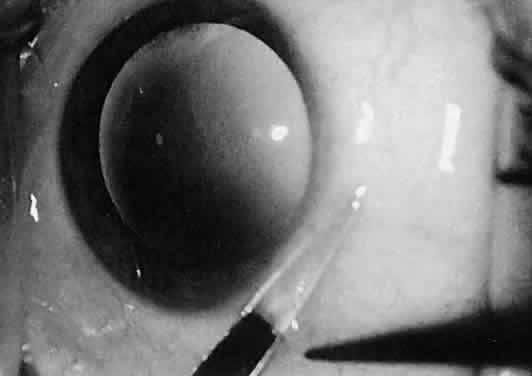

Iris tissue is extremely delicate, and it should be handled with great care. A Bonn 0.12-mm forceps is best used for handling iris tissue, although the iris should be grasped only when it is being incised or sutured. When a peripheral iridectomy is made, the iris may be grasped with a Bonn 0.12-mm fixation forceps or a smooth forceps. With gentle traction, the iris may be pulled through the surgical incision and then incised with Vannas scissors (Fig. 41). The iris then may be repositioned with a viscoelastic substance or a spatula, if necessary. If the iris must be sutured, Bonn forceps or smooth forceps should be used, as should a blood vessel round needle, which does not have a cutting edge and will thus avoid unnecessary tearing of the iris stroma.

Fig. 41. The iris is pulled through a limbal incision with a 0.12-mm fixation forceps and incised with Dewecker's scissors. In this way, a peripheral iridectomy is performed.